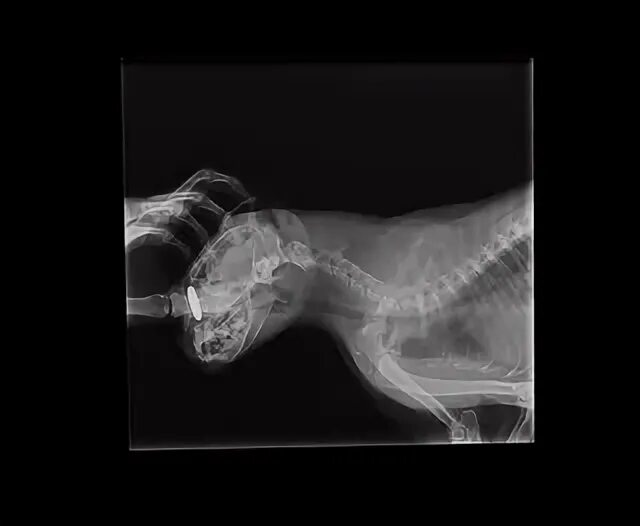

Почему кот кашляет и вытягивает